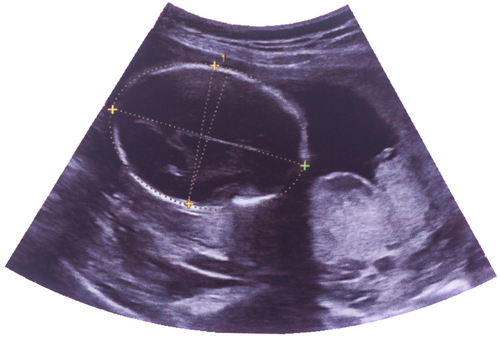

With the sex ratio in Punjab in dismal figures, the state's Health Department announced on Monday that all ultrasound centres across the state would be put under surveillance.

"891 girls per 1,000 boys as per civil registration system in January 2017 is a matter of serious concern," Punjab Health Minister Brahm Mohindra said here in a statement. "The Punjab government has framed a comprehensive policy to check the lower count of a girl child born per 1,000 boys' births by ensuring the proper implementation of a total ban on the pre-diagnostic tests.

"The Health Department has issued set of strict instructions by which all the ultrasound centres would put under 24x7 online surveillance while the police verification of doctors and other staff posted at such centres has been made mandatory," he said, regretting that the sex ratio of the state could not be improved as per the set targets.